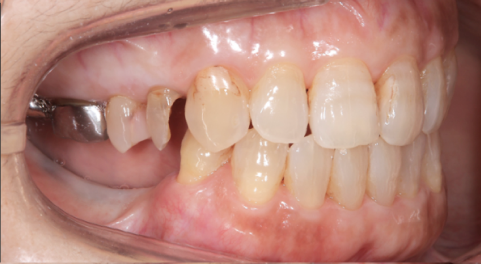

主訴:左下の歯が外れた。

治療概要:左下の歯が外れたことがきっかけで来院されました。右下と左上には歯がない状態でした。

外れた左下の歯ですが、歯茎から出ている歯の部分が明らかに短く、この状態で被せ直しをしても維持力がないためすぐに外れてしまう事が予想されました。

また、奥歯がないためこの歯には噛む時の力が過剰にかかってしまいます。

この方の場合右の歯も少なく、主訴である左下の歯だけ治療をしたとしても今残っている歯も含めてどんどん悪くなることが予想されました。

このような理由で口腔全体を含めた「全顎の治療」計画を提案させていただきました。

現状残っている歯の状態から、この患者さまは「生理的咬合」であると診断し、現状噛んでいる歯の位置の修正とは行わずに、歯がないところ、歯が欠けているところを治すだけで安定すると考え治療を行っています。